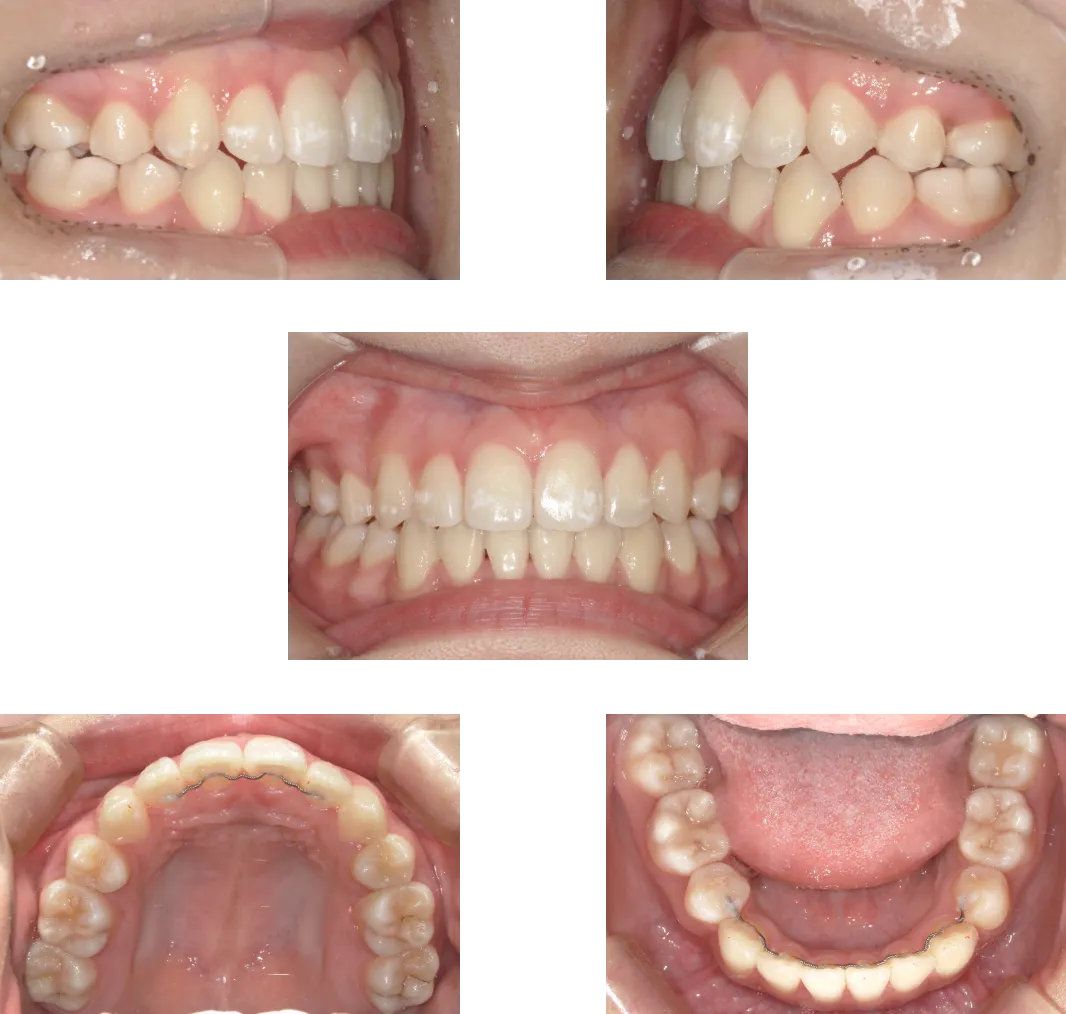

上顎前突 -7歳-

• Before

• After

診断

過蓋咬合を伴う重度骨格性上顎前突

治療期間

2年

抜歯

なし

料金

600,000+550,000円(調整料を含む。2期開始時分析料別途発生)

リスク

痛み、軽度の歯根吸収、術後の変化